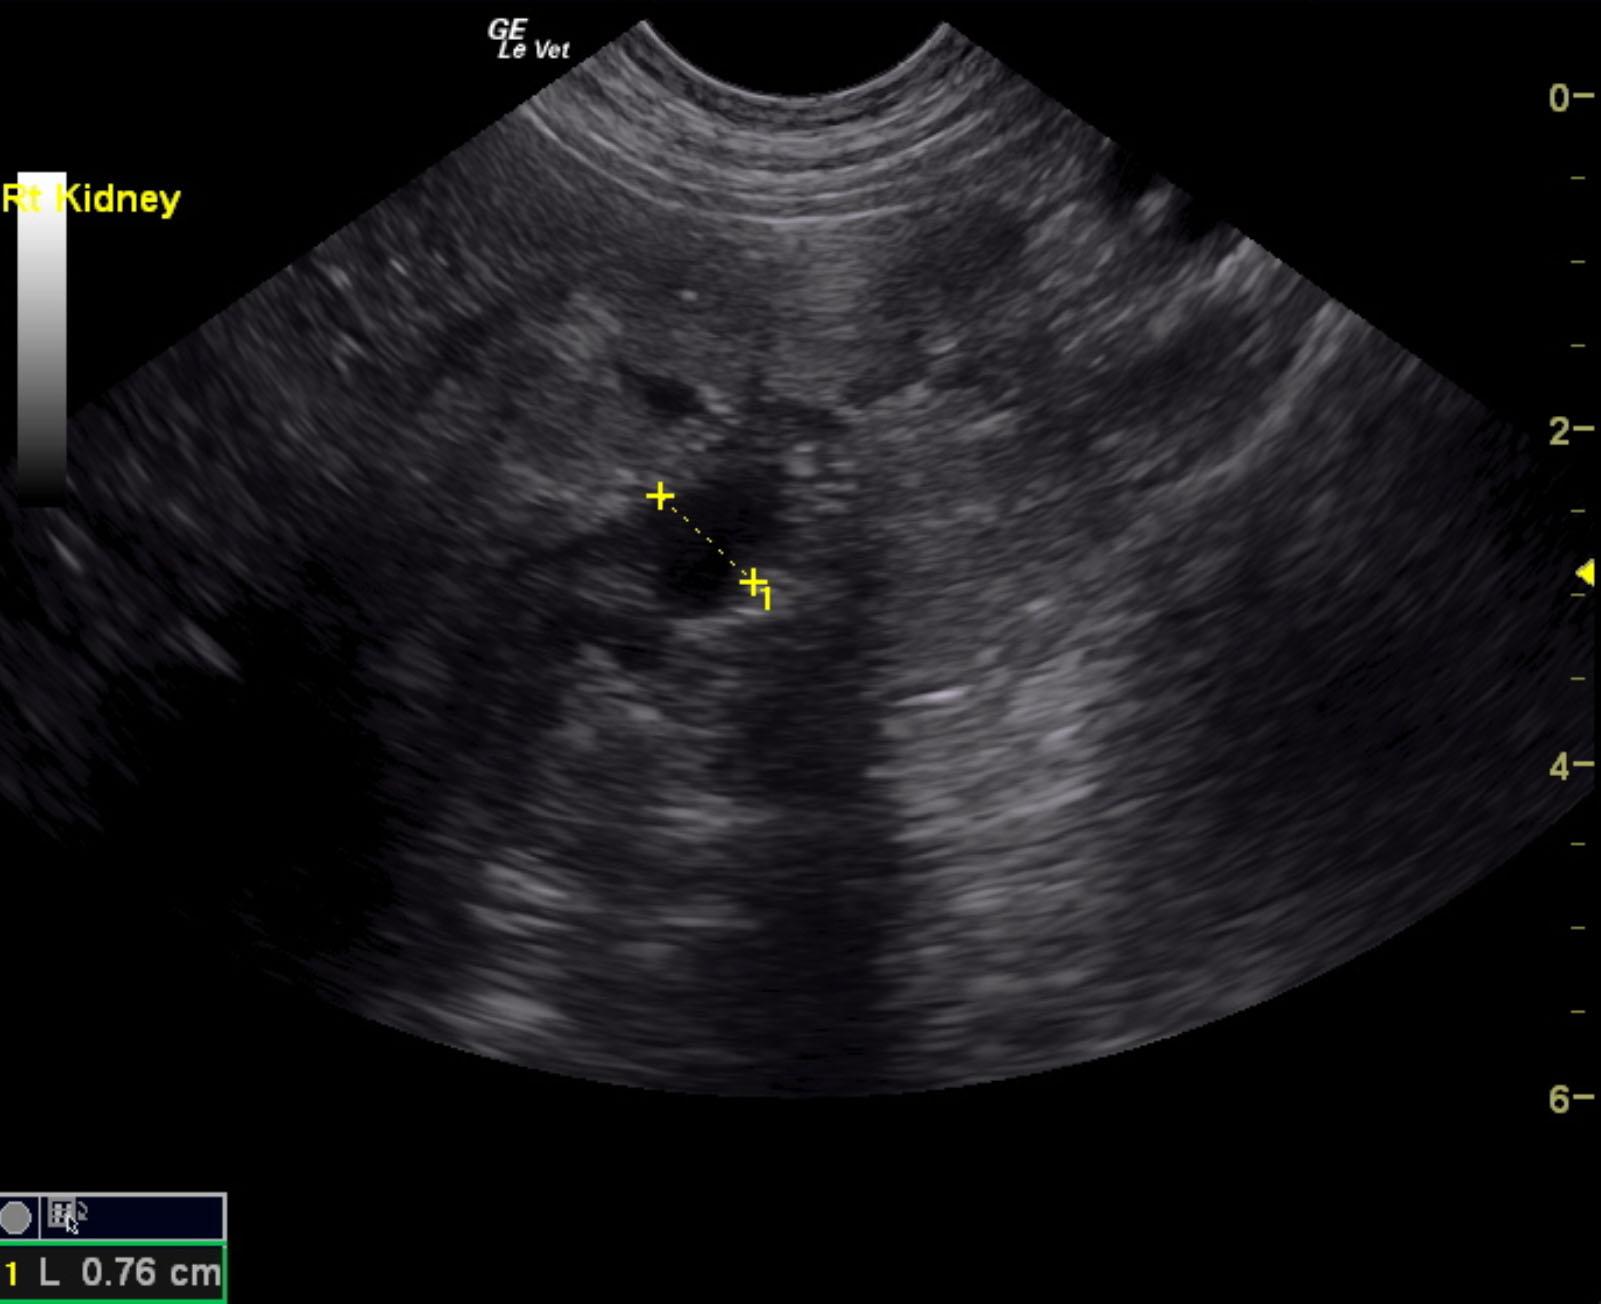

Both kidneys in this patient presented significant, dysplastic changes with cortical irregularity and disruption of the corticomedullary structure. A significant amount of microinfarctions and hyperechoic areas of mineralization and fibrosis as well as cortical cysts were noted. Color flow assessment of the renal cortices was significantly subnormal. This is consistent with chronic disease. The left kidney measured 5.08 cm. The right kidney presented pyelectasia that measured 0.76 cm. The right kidney measured 5.04 cm.